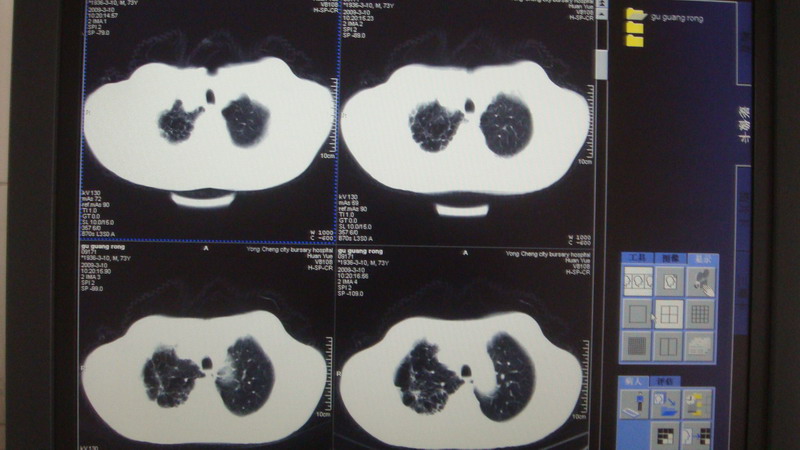

以下是引用光影相伴在2009-3-11 17:27:00的发言:[br]支持 右肺下叶周围型肺癌伴右肺门纵隔淋巴结转移;右上肺继发型肺结核(硬结\\纤维灶);右侧少量胸胸腔积液。另:不排除右侧胸膜转移可能。

以下是引用随光逐影在2009-3-11 16:57:00的发言:[br]支持 右肺下叶周围型肺癌伴右肺门纵隔淋巴结转移;右上肺继发型肺结核(硬结\\纤维灶);右侧少量胸胸腔积液。另:不排除右侧胸膜转移可能。

以下是引用草之原在2009-3-11 19:03:00的发言:[br]支持 右肺下叶周围型肺癌伴右肺门纵隔淋巴结转移;右上肺继发型肺结核(硬结\\纤维灶);右侧少量胸胸腔积液。另:不排除右侧胸膜转移可能。